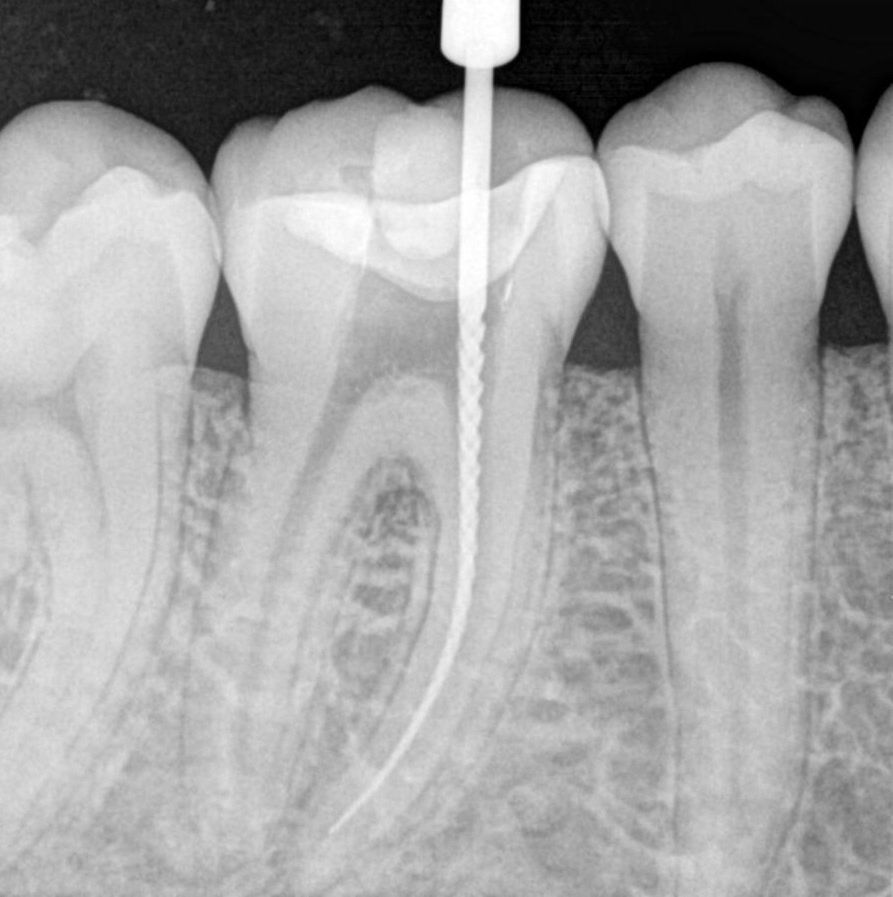

Root Canal Radiograph Endodontics Xray    cone beam computed tomography (cbct) has become an indispensable diagnostic imaging tool in.   imaging technology aids in the diagnosis of endodontic pathosis and canal morphology, assessing root and alveolar. Describe the importance of radiographs in endodontic diagnosis, treatment, and postoperative evaluation. Dental radiography allows for the. Dental radiography allows for the. Endodontics Xray.